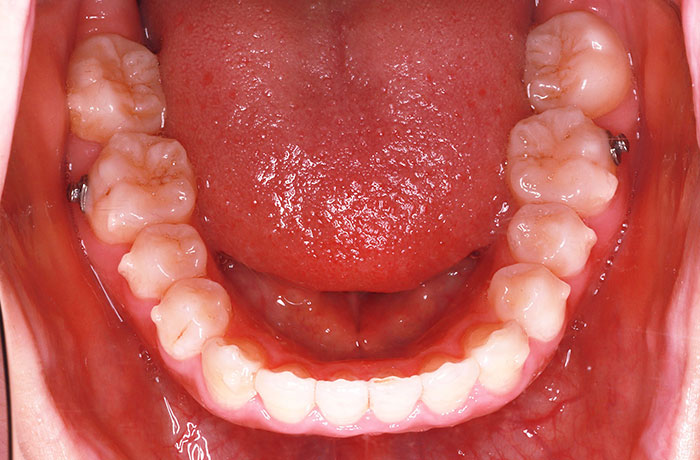

I様

治療前

before

年齢 34歳

性別 男性

治療名称 マウスピース型カスタムメイド矯正歯科装置(インビザライン)・コンプリヘンシブパッケージ(フルパッケージ)

総額治療費用 770,000円(税込) 金額備考 検査・診断料33,000円含む

治療期間 8か月 通院頻度など 40日ごと

その他治療に関する情報 1枚につき10日装着を指示しました。

患者の症状 上顎前歯の凸凹

治療方法 非抜歯で、マウスピース型カスタムメイド矯正歯科装置による矯正

治療結果 歯並び、咬み合わせが良くなりました。

その他治療に関する情報 歯並びをより良くするために追加でアライナーを発注しました。

リスク/副作用 スペース不足を解消するために歯と歯の間をわずかに削合しました。